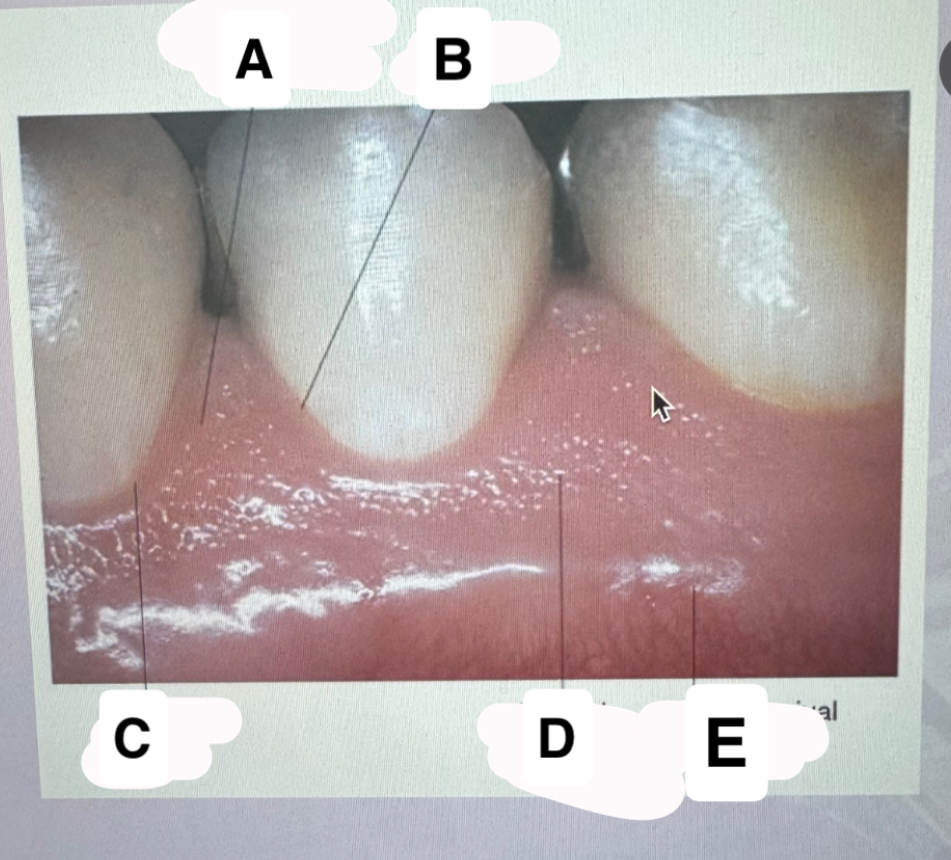

<p>Identify A</p>

Interdental papilla

<p>Identify B </p>

Sulcus

<p>Identify C</p>

Gingival margin

<p>Identify D</p>

Normal stippling of tissue

Mucogingival

junction